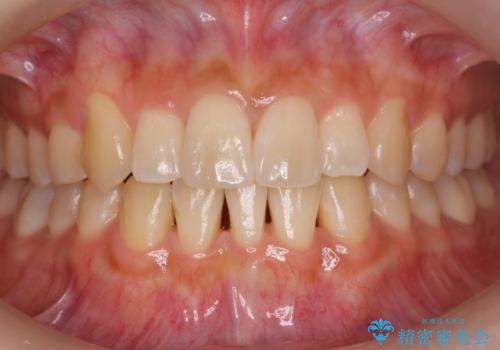

[ 総合歯科診療 ] がたつきの改善とセラミック治療

![[ 総合歯科診療 ] がたつきの改善とセラミック治療の症例 治療前](https://seimitsushinbi.jp/wp/wp-content/uploads/2024/03/f0f438a14c56b185411649f48b5b188c-500x350.jpg?v=1710833163)

![[ 総合歯科診療 ] がたつきの改善とセラミック治療の症例 治療後](https://seimitsushinbi.jp/wp/wp-content/uploads/2024/03/7212917eb9c4ef33050c52e7f9724490-500x350.jpg?v=1710833188)